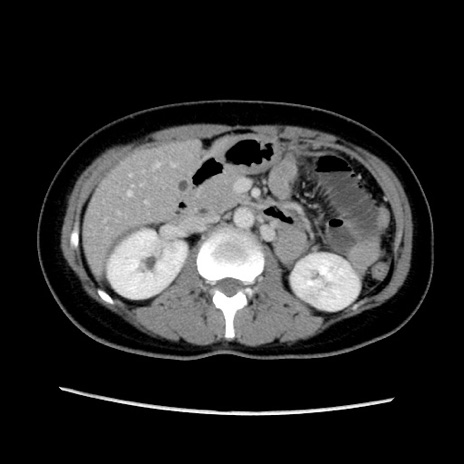

症例39(横断像)

【症例】40歳代女性

【主訴】上下腹部痛

【現病歴】2日目から下腹部痛あり。夜間は痛みで眠れなかった。昨日より上腹部痛と下痢が出現。臥位で痛みは軽快したため、休んでいた。本日になって臥位でも立位でも痛みが強くなってきたため救急要請。

【既往歴】子宮内膜症

【身体所見】部:平坦・軟、左上下腹部に圧痛あり、反跳痛あり。

【データ】WBC 21800、CRP 26.78